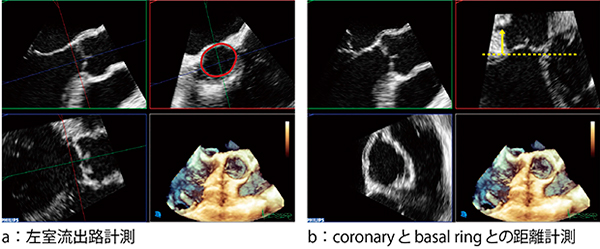

TAVRでは,術前の心機能評価や石灰化評価,弁輪径の評価などが非常に重要になる。現在では,デバイスのサイズの決定や石灰化評価,さらにはcoronaryとbasal ringとの距離計測は,CT検査で行われることが非常に多い。Live 3D TEEトランスジューサには,世界で初めて素子にPureWaveクリスタル(単結晶)を採用し,高画質で高精細な画像を描出することが可能となった。このことによってLive 3D TEE Imageの画質は飛躍的に向上し,CT検査で行われてきたSHD治療の術前に重要なさまざまな計測項目の正確な測定,さらに事前に解剖学的な把握が容易となり,本来のエコー検査のメリットを発揮してきている2),4)(図4)。

図4 Live 3D TEEを用いたさまざまな計測